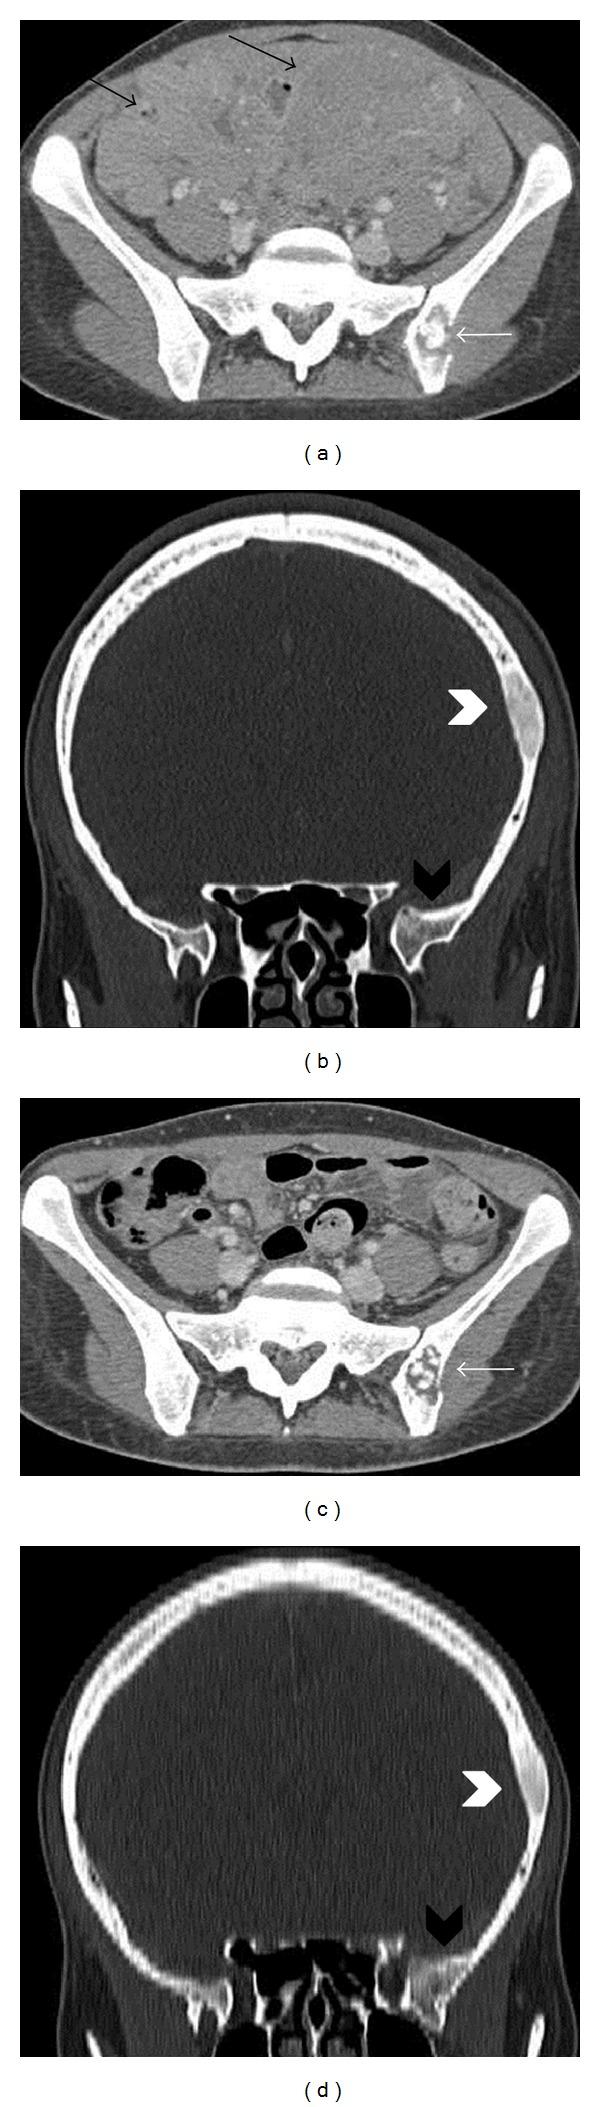

Burkitt's lymphoma is a rare non-Hodgkin's lymphoma which can occasionally involve the ovary and may cause confusion for the clinician since its presentation might mimic other much more frequent tumors. We present a case of a 23-year-old woman with sporadic Burkitt's lymphoma presented as advanced ovarian cancer with bilateral ovarian masses, peritoneal carcinomatosis, ascites, and marked elevation of CA-125. Liver involvement and atypical bone lesions, such as the cranial vault and the iliac wing, were also detected without evidence of lymphadenopathy. We describe the MRI and CT findings of simultaneous ovarian and bone lesions, which have never been reported in literature in a patient with Burkitt's lymphoma, before and after one cycle of chemotherapy. In evaluating any ovarian neoplasm in a young woman, Burkitt's lymphoma should be considered as a possibility, particularly if associated with bone lesions. MRI is the most useful tool to characterize the ovarian lesions and suggest the diagnosis before the histopathological results.

伯基特淋巴瘤是一种罕见的非霍奇金淋巴瘤,偶尔可累及卵巢,因其表现可能类似其他更常见的肿瘤,这可能会给临床医生带来困惑。我们报告一例23岁女性散发性伯基特淋巴瘤,表现为晚期卵巢癌,伴有双侧卵巢肿块、腹膜癌转移、腹水及CA-125显著升高。还检测到肝脏受累以及颅骨穹窿和髂骨翼等非典型骨病变,且无淋巴结病证据。我们描述了该患者在化疗一个周期前后同时出现的卵巢和骨病变的MRI及CT表现,此前文献中从未报道过伯基特淋巴瘤患者出现这种情况。在评估年轻女性的任何卵巢肿瘤时,应考虑伯基特淋巴瘤的可能性,尤其是伴有骨病变时。MRI是在组织病理学结果出来之前,用于描述卵巢病变特征并提示诊断的最有用工具。